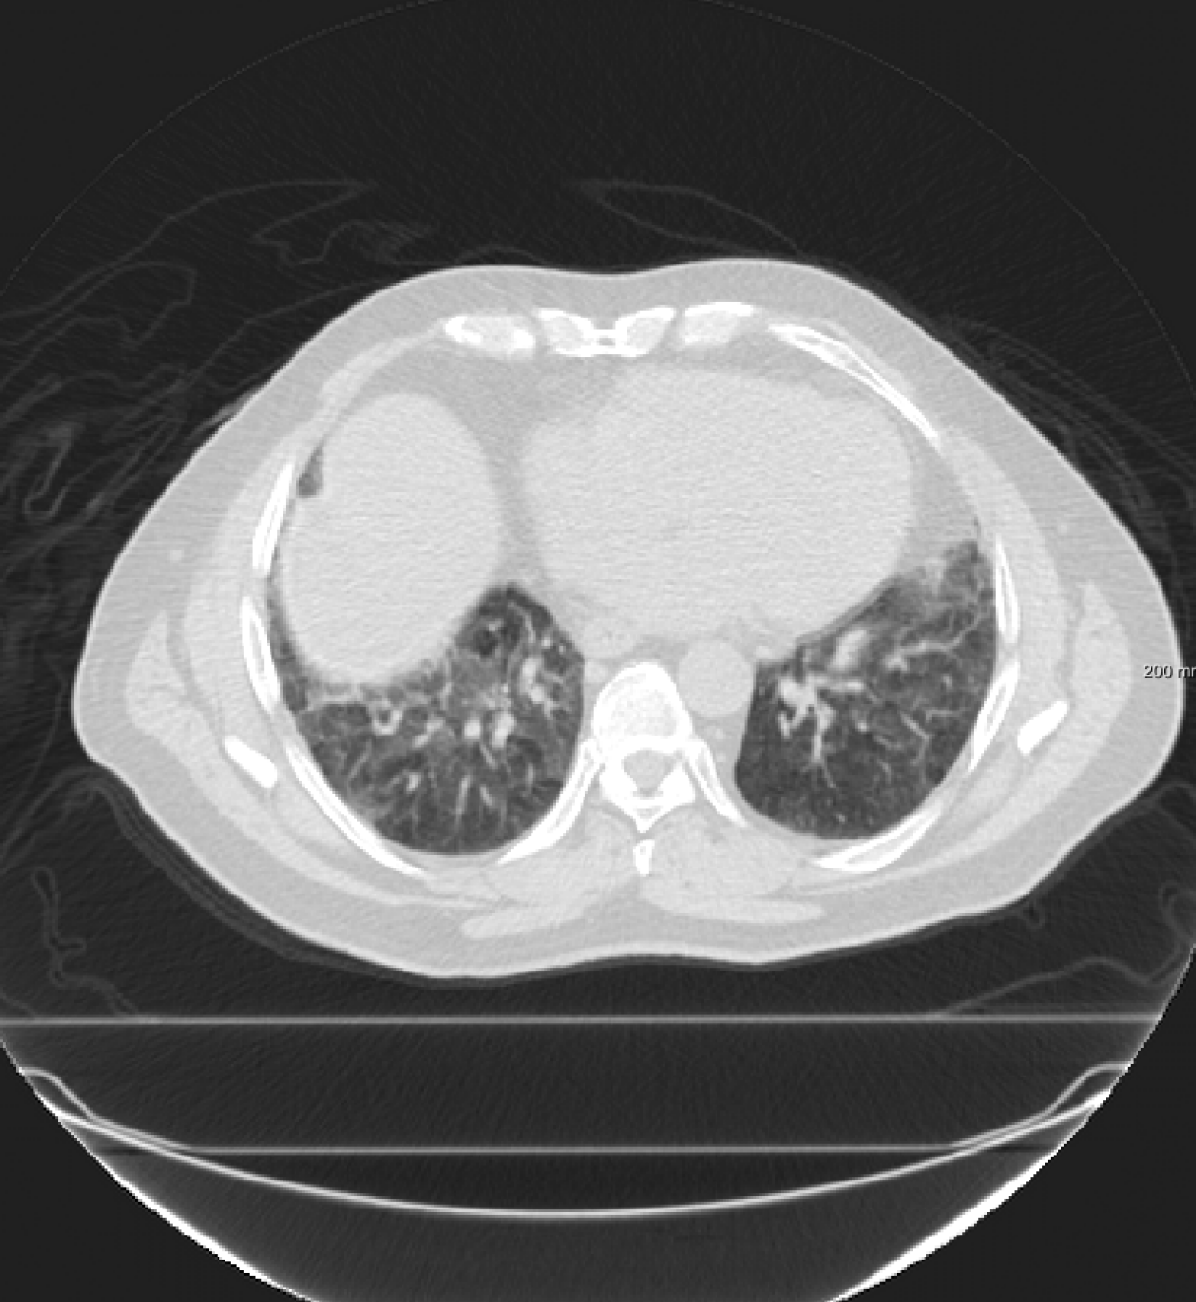

respiratory motion: We simulate respiratory motion with three components similar to Hub et al. (2009) as follows: Expansion of the chest in the transversal plane with a maximum scaling factor of 1.12; Transition of the diaphragm in cranio-caudal direction with a maximum deformation of ; Random deformation using the single frequency method. In order to locate the diaphragm, an automatically detected lung mask is used.

In the SPREAD database, 21 pairs of 3D chest CT images are available with a baseline and a follow-up image in each pair. The follow-up images are taken after 30 months. Both images are acquired in the inhale phase. Patients in this study are aged between 49 and 78 years old. The size of the images is approximately with a mean voxel size of mm. About 100 well-distributed corresponding landmarks were previously selected (Staring et al., 2014) semi-automatically on distinctive locations (Murphy et al., 2011). Two cases (12 and 19) are excluded because of the high uncertainty in the landmarks annotation (Staring et al., 2014).

In the DIR-Lab-COPDgene database, ten cases with severe breathing disorders are available in inhale and exhale phases. The average image size and the average voxel size are and mm, respectively. In each pair, 300 landmarks are annotated.

In the DIR-Lab-4DCT database ten cases are available. We use two phases of the available data: maximum inhalation and maximum exhalation. The size of the images is about with an average voxel size of mm.